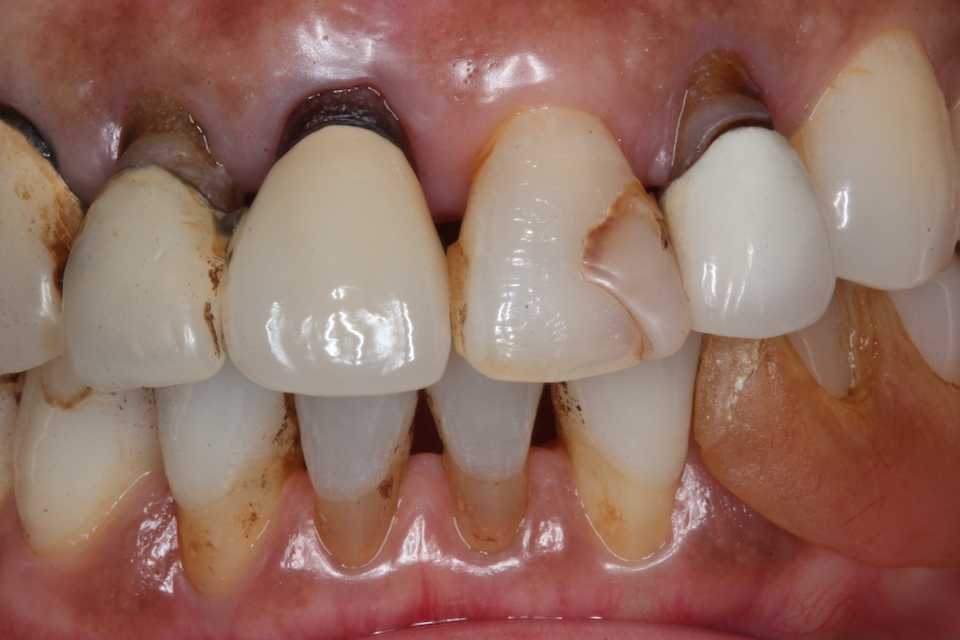

70代女性、右上2、歯根破折、左上2、SK脱離このところの異常な熱波続きでついふらふらと意識が遠のき、顔面から転倒。歯が折れてしまった。特に右上は歯根も破折しているので、通常は抜歯するしかないのだけれど、α-TCPで接着固定して、それをCRで巻いてついでに歯冠も作った。破折歯根上のCRということです。転倒前beforeafter3〜3をスーパーボンド併用で連結固定している。